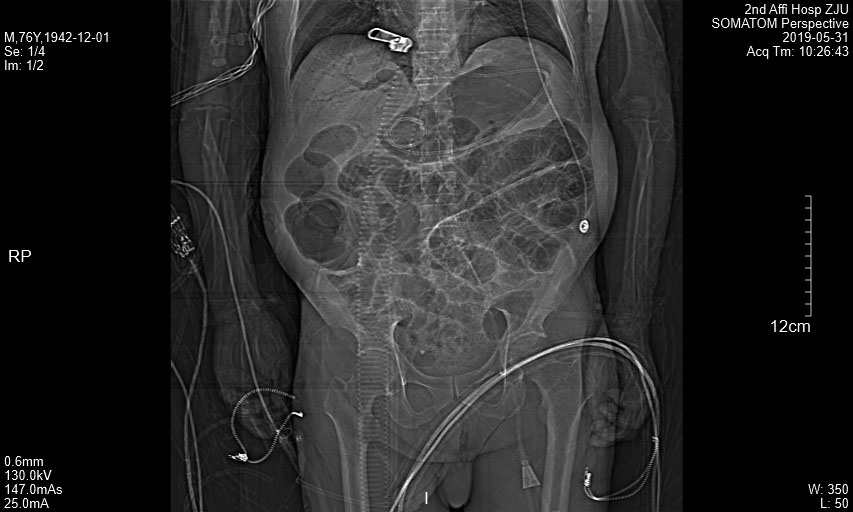

附图2 患者冠状面CT图